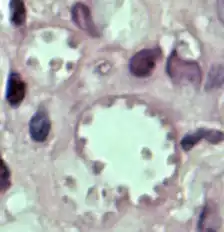

Leishmania mexicana in a biopsy specimen from a skin lesion stained with H&E. The amastigotes are lining the walls of two vacuoles, a typical arrangement. The species identification was derived from culture followed by isoenzyme analysis. | |